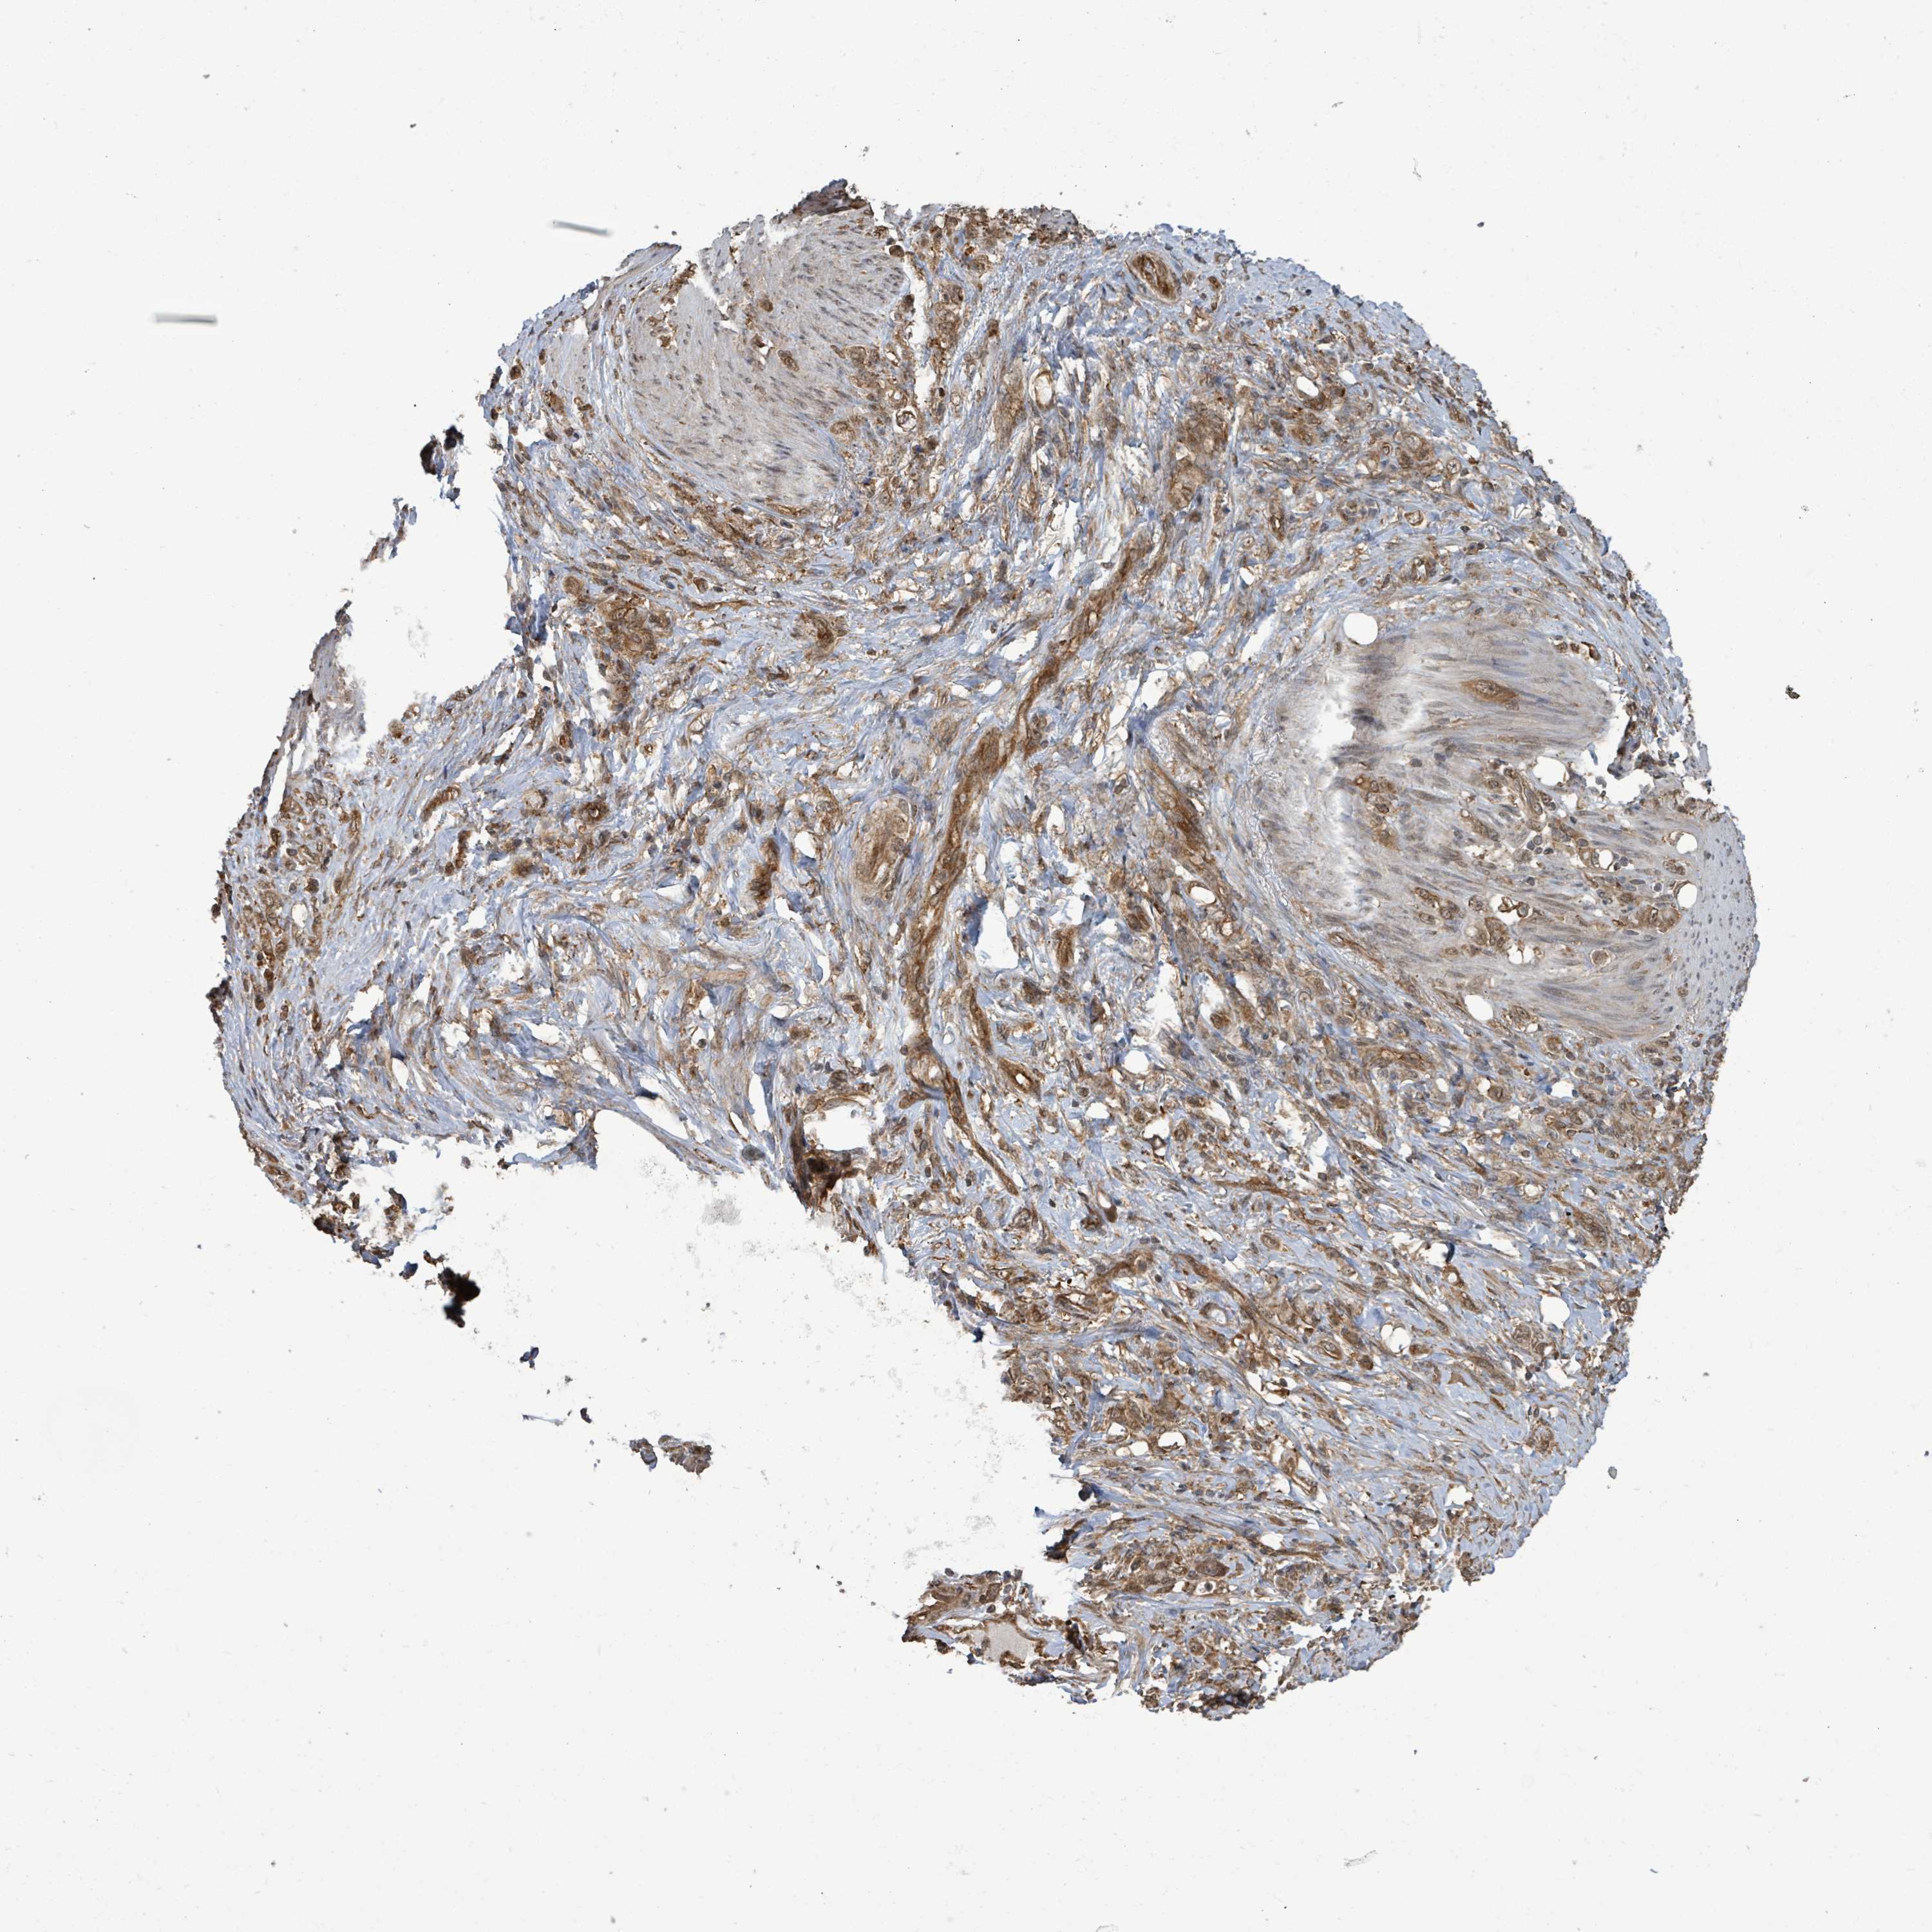

STOMACH CANCER - Protein expressioni

A mouse-over function shows sample information and annotation data. Click on an image to view it in a full screen mode. Samples can be filtered based on level of antibody staining by selecting one or several of the following categories: high, medium, low and not detected. The assay and annotation is described here.

Note that samples used for immunohistochemistry by the Human Protein Atlas do not correspond to samples in the TCGA dataset.

Antibody stainingi

Antibody staining in the annotated cell types in the current human tissue is reported as not detected, low, medium, or high, based on conventional immunohistochemistry profiling in selected tissues. This score is based on the combination of the staining intensity and fraction of stained cells.

Each image is clickable and will lead to virtual microscopy that enables deeper exploration of all samples and also displays staining intensity scores, fraction scores and subcellular localization as well as patient and tissue information for each sample.

Antibody HPA044617

Antibody HPA052450

Staining

High

Medium

Low

Not detected

Intensity

Strong

Moderate

Weak

Negative

Quantity

>75%

75%-25%

<25%

None

Location

Nuclear

Cytoplasmic/membranous

Cytoplasmic/membranous,nuclear

Adenocarcinoma, NOS